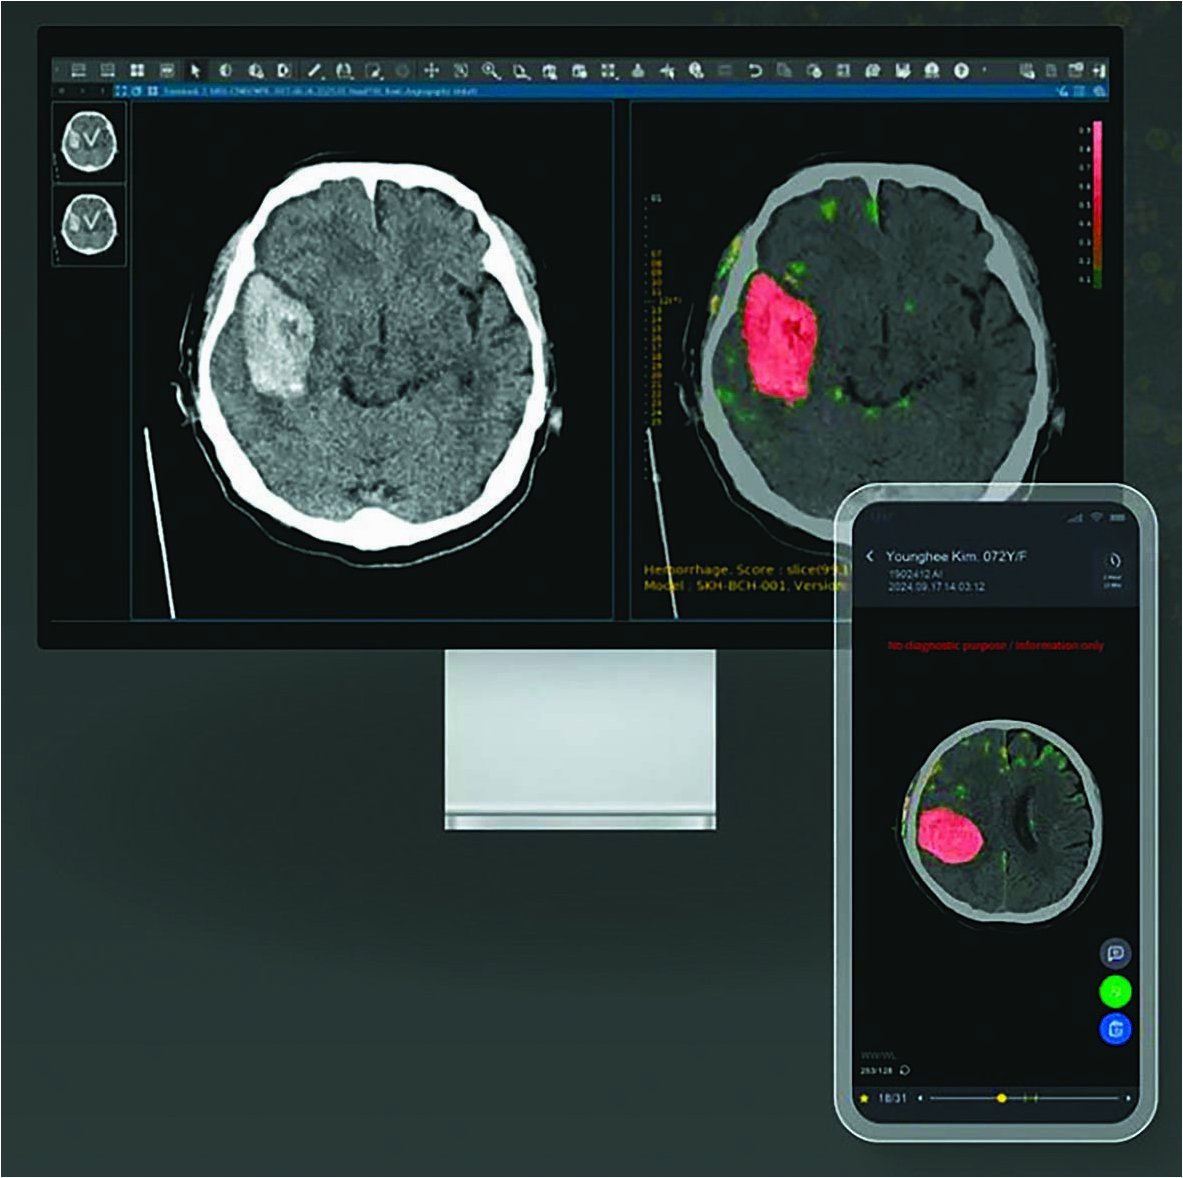

뇌 자기공명영상(MRI)을 단 몇 초 만에 분석하여 신경 질환을 97.5%의 정확도로 진단하고, 환자의 긴급 치료 필요성을 예측하는 혁신적인 인공지능(AI) 기반 모델 '프리마(Prima)'가 개발되었습니다. 이 기술은 영상 검사 즉시 환자에게 피드백을 제공하며, 진단된 질환에 따라 최적의 세부 전문의에게 알림을 추천하는 기능까지 갖추고 있습니다미국 미시간대 의대 토드 홀런 교수팀이 네이처 바이오메디컬 엔지니어링에 발표한 이 연구는 신경영상 분야에 획기적인 변화를 가져올 것으로 기대됩니다.

논문의 제1 저자인 이웨이 뤼 박사는 "뇌 MRI 판독 시 정확성만큼이나 신속한 판독이 적시 진단과 치료 성과 향상에 매우 중요하다"고 강조했습니다프리마는 여러 핵심 단계에서 정확성을 희생하지 않으면서 임상 진료를 효율화할 수 있음을 보여주며, 빠르고 정확한 정보 제공을 통해 의사와 의료 시스템의 부담을 줄여줄 잠재력을 지니고 있습니다.

AI 기반 뇌 MRI 판독 모델 '프리마'와 'BrainIAC'은 진단의 정확성과 신속성을 획기적으로 향상시키며 의료 시스템의 부담을 줄이고 있습니다더불어 정부의 의료 접근성 개선 노력은 의료 불균형 해소에 기여할 것으로 보입니다.